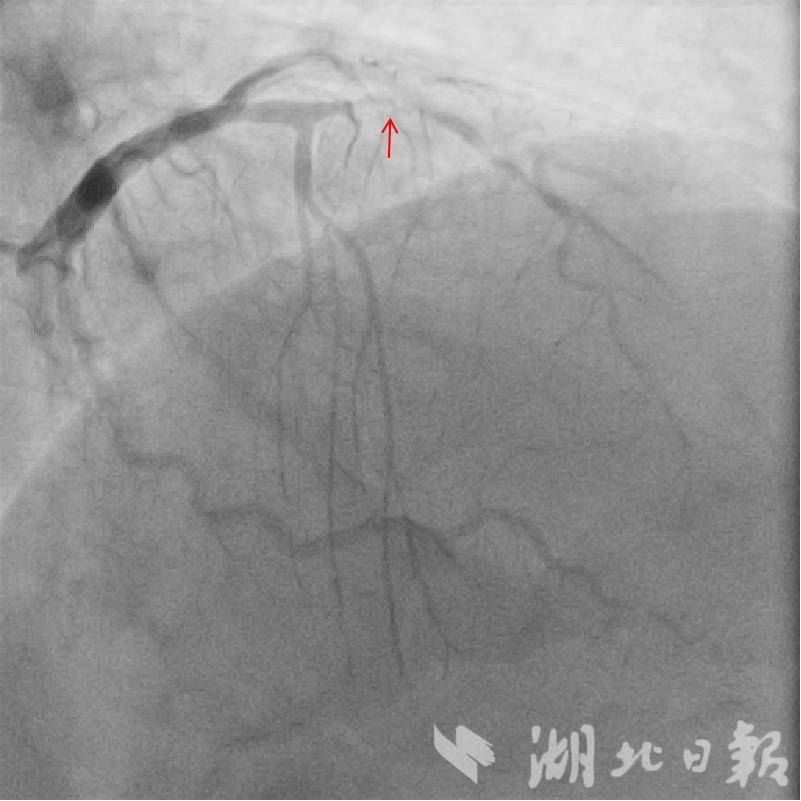

来自湖北宜昌的夏先生,因急性冠脉综合征接受冠脉造影检查时,发现左前降支中段几乎闭塞,同时出现严重造影剂过敏反应,引发顽固性低血压、心室颤动等,经紧急抢救才脱离危险,支架置入手术也被迫中止。常规心脏介入手术离不开造影剂,它能让血管在X 射线下显影,帮助医生制定手术策略、定位支架并评估术后效果,但夏先生的过敏情况让传统方案彻底“碰壁”。不愿放弃微创治疗的他,最终求助于该院心血管医院冠心病Ⅲ 科王朗主任。

10月 27日,在麻醉科的配合下,手术正式开展。王朗团队仅靠X 线指引,将导引导管、导引钢丝精准送入病变血管,通过预扩张球囊打开闭塞部位后,送入IVUS 导管。借助这一“血管内超声探头”,团队精确测量病变参数、确定支架规格及定位点,再以分支血管导丝为标记,成功完成支架置入。术后IVUS 复查显示,支架位置精准、膨胀充分、贴壁完美,手术圆满成功,夏先生转危为安。